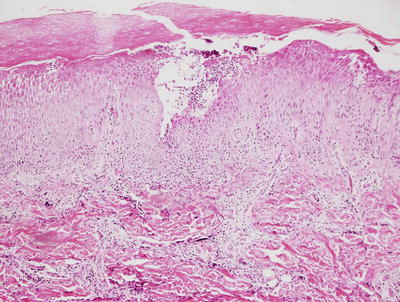

3.1.2 Histology

The histologic findings of acropustulosis of infancy are not specific, but characteristic of this entity. The epidermis has foci of spongiosis with microvesiculation [2] (Fig. 3.3). Neutrophilic abscesses are present within the vesicles (Fig. 3.4). Acute lesions do not have parakeratosis, although this is a common finding in more established lesions. Less commonly, eosinophils may be present within the microvesicles [3].

Fig. 3.3

Histologic features of acropustulosis of infancy include intraepidermal spongiosis and clusters of neutrophils within the stratum corneum